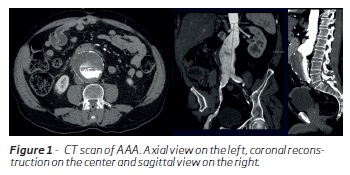

A new contrast enhanced CT scan was made and showed an infrarenal aortic aneurysm with a 2.5 mm neck, 19mm neck's diameter and 67 mm maximum diameter. The right common iliac artery aneurysm had 35 mm diameter. The aneurysm sac had a circunferencial non fissured intraluminal homogeneous thrombus and moderate calcificacion. The aneurysm neck did not have any significant thrombus or calcification. No lesions were detected in the thoracic aorta. (Figure 1)